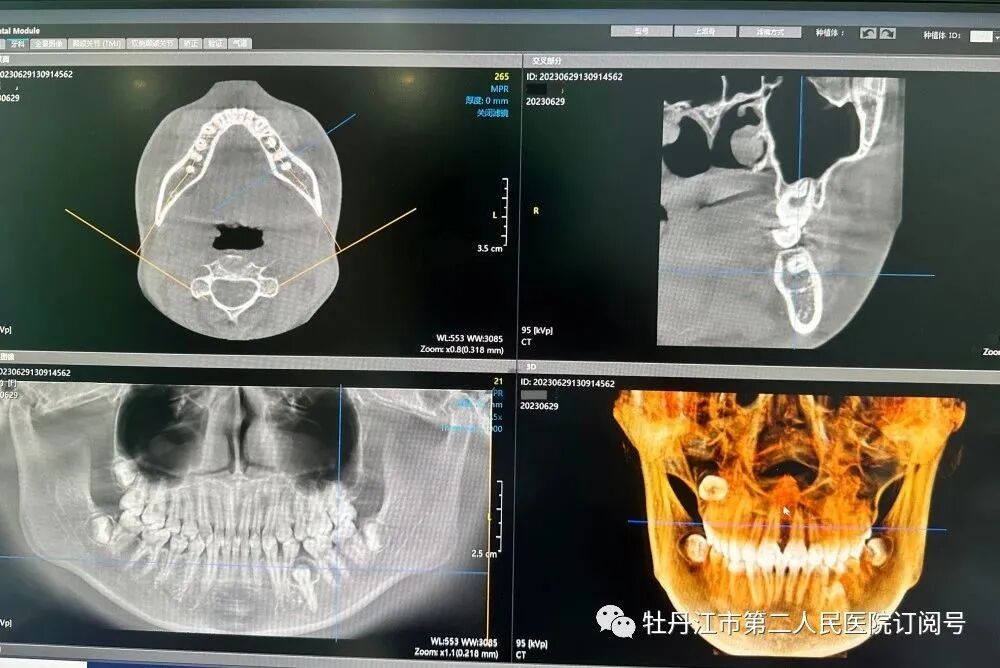

KaVo 3D eXam CBCT(口腔颌面锥形束CT)是一款集三维CT影像和常规二维全景影像拍摄为一体的口腔专业椎束CT,可充分满足种植、正畸、牙体牙髓、颌面外科等各种影像诊断及手术治疗的需求。该设备的投入使用将为口腔疾病的诊断及治疗提供强有力的支持,使口腔及颌面部疾病患者享受到更加精准的诊断与治疗服务。

KaVo 3D eXam CBCT可拍摄口腔全景片、口腔侧位片、口腔CT。拍摄全景片是口腔治疗之前一个很重要的检查过程,通过全景片,医生可以清楚看到牙齿、牙槽骨情况,能帮助医生在智齿拔除、牙周治疗、根管治疗、正畸做出风险评估、正确诊断,进而指导整个治疗方案。

口腔CT可以呈现整个头颅情况,在颌面外科中能了解智齿与神经管的关系,颌骨囊肿大小、边界、对周围组织影响,颌骨骨折,从而帮助医生制定方案、提高手术安全性。在牙体牙髓治疗中能了解牙齿解剖形态、牙槽骨吸收情况,辅助医生做好根管治疗、牙周治疗具有重大意义。在种植方面可为医生提供高精准度的骨质密度、距神经、血管、上颌窦距离、牙间距离数据,使医生在选择种植体和种植方向、是否需要植骨时能有据可依。